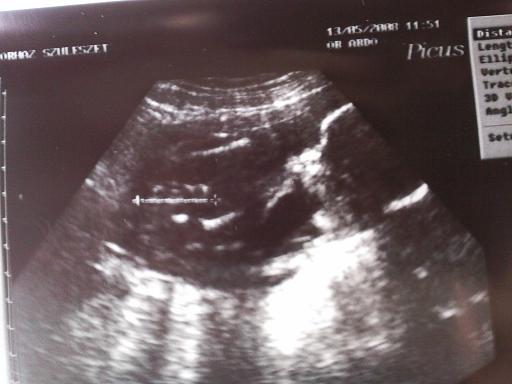

Jaj Lányok köszönöm szépen annyira aranyosak vagytok Én meg annyira BOLDOG!! Nem tudok még minidg mit kezdeni a hírrel annyira hihetetlen!!!

Felrakom a képet nem a legszuperebb de szerintem látni, hogy mit muatat a vonal!! Remélem Ti is látjátok ?! :):)

Hát az biztos, hogy Nekem sem mondana semmit a kép ha elém tette volna de így többedszerre nézve egyre jobban látom. Szemből van a baba a fütyi kétoldalán a lábai, fehérítenek a combcsontjai!! :lol: